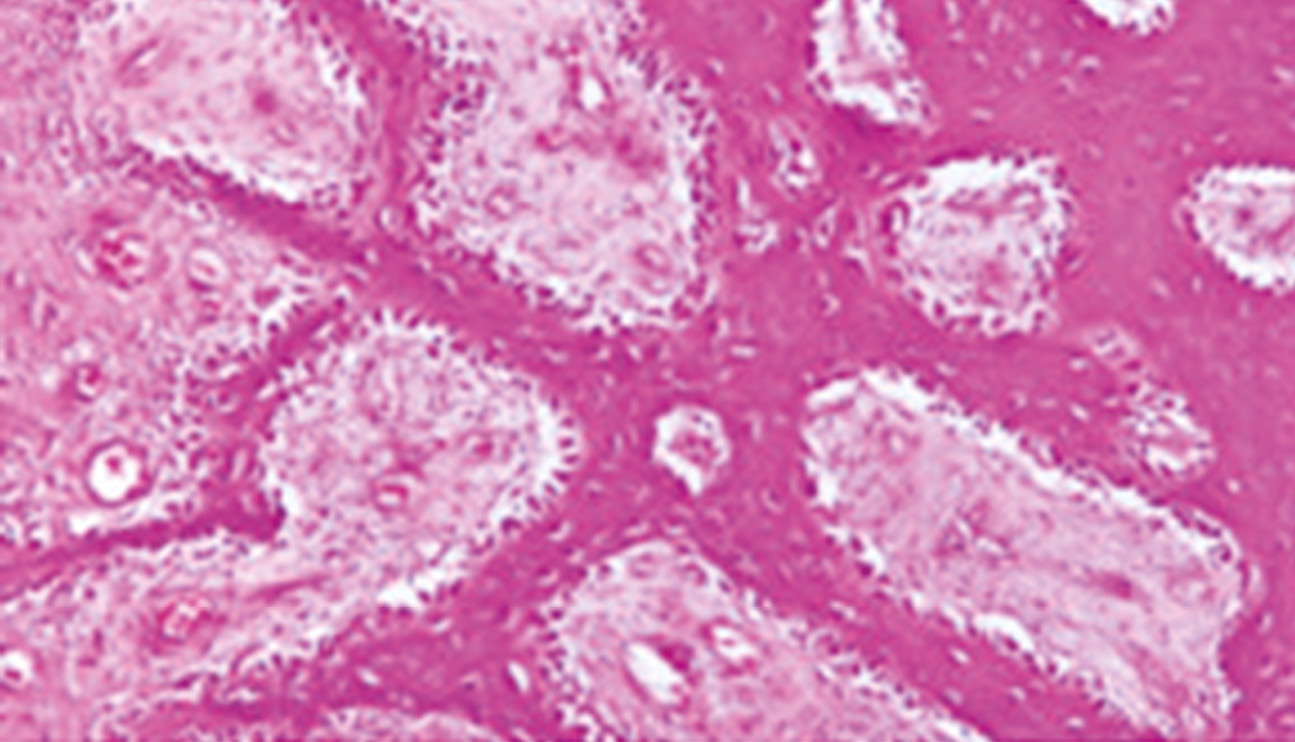

Применение в эксперименте новейшего дистракционного устройства объективно показало возможность построения регенератов костной ткани при непрерывной дистракции в различных темпах. При этом морфологическое исследование новообразованных регенератов выявило наиболее гистоморфологически зрелую костную ткань в темпе 2 мм в сутки (рис. 7).

Рис. 7. Губчатая кость, полученная с темпом непрерывной дистракции 2 мм в сутки: участок выраженного роста и ремоделирования костной ткани; новообразованные костные трабекулы — узкие и извитые; остеоны — с новообразованной костной тканью, большим числом лакун с остеобластами и остеоцитами; каналы — с разрастанием отёчной соединительной ткани, с расширенными полнокровными сосудами, большим количеством остеобластов, формирующих палисады на границах с костной тканью; остеокласты единичные. Окраска гематоксилином и эозином, ×120.

Fig. 7. Spongy bone obtained with a continuous distraction rate of 2 mm per day: area of pronounced growth and remodeling of bone tissue; newly formed bone trabeculae are narrow and tortuous; osteons with newly formed bone tissue, a large number of gaps with osteoblasts and osteocytes; channels with proliferation of edematous connective tissue, with dilated full-blooded vessels, a large number of osteoblasts forming palisades at the borders with bone tissue; single osteoclasts. Staining with hematoxylin and eosin, ×120.